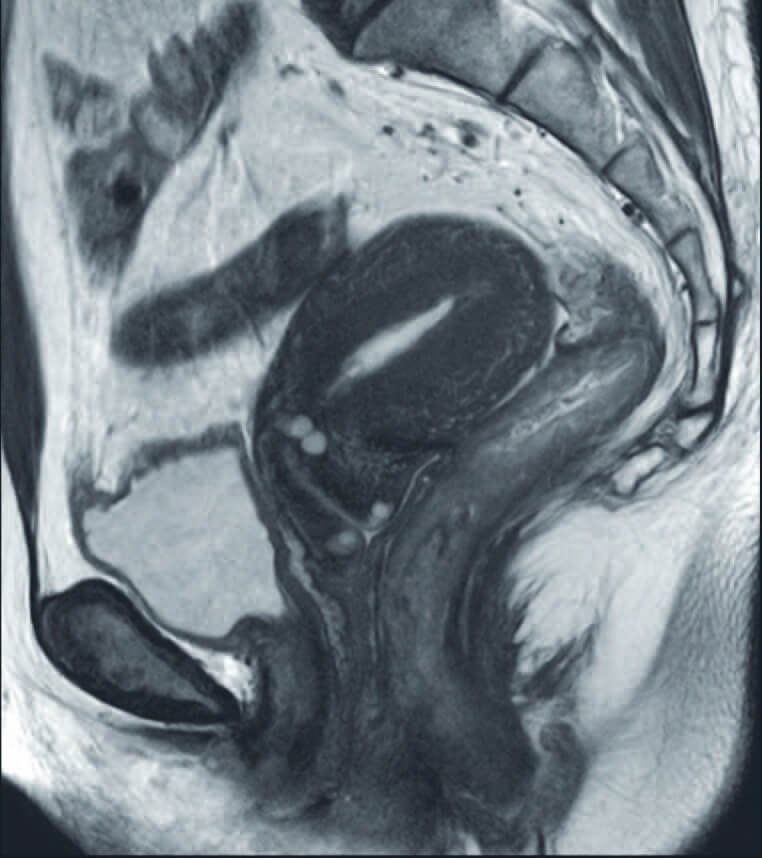

Pelvis